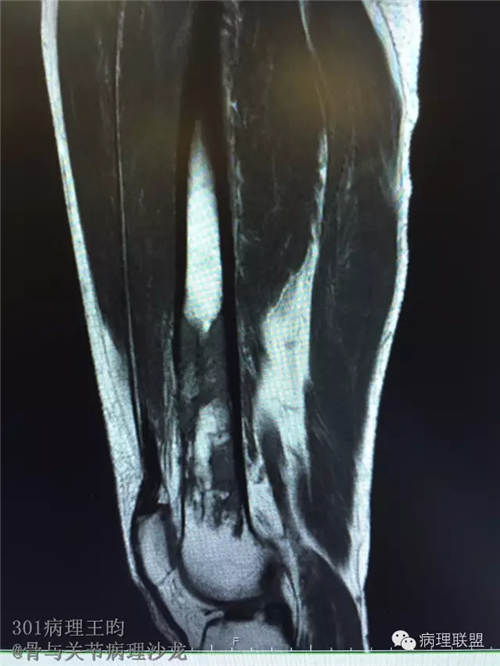

右股骨髓内高分化低级别骨肉瘤or骨纤维异常增殖症(Fibrous Dysplasia)?

男,36岁,活动后疼痛,发现右股骨远端肿瘤。